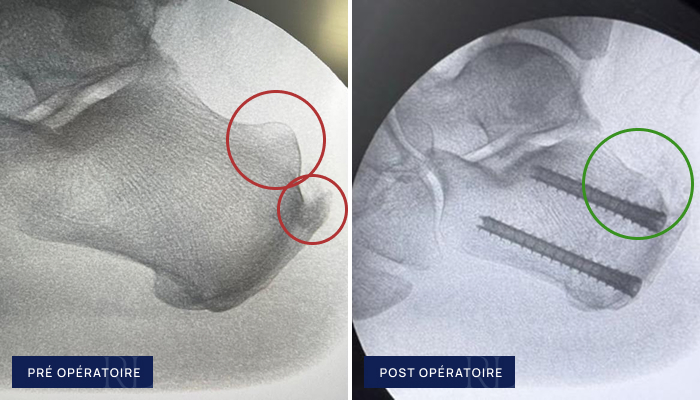

Radiographies pré et post opératoire de Tendinopathie d’Achille (Haglund)

À gauche : Conflit de Haglund

À droite : Resection mini invasive